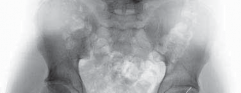

2. The trochanteric fragment is anatomically reduced and fixed with two or three 3.5-mm cortical screws (

TECH FIG 7

).

1. Screw heads are countersunk to avoid irritation of the fascia lata.

40. In women, meticulous fascial closure and subcutaneous tissue adaptation is performed, to prevent saddlebag deformity. TECH FIG 7 • A. Preoperative radiograph in a patient with coxa profunda. B. Postoperative view of the same patient after circumferential detachment of the labrum and trimming of the acetabulum. The labrum is refixated with eight bone anchors. The trochanter is

A B reattached with two 3.5-mm screws.